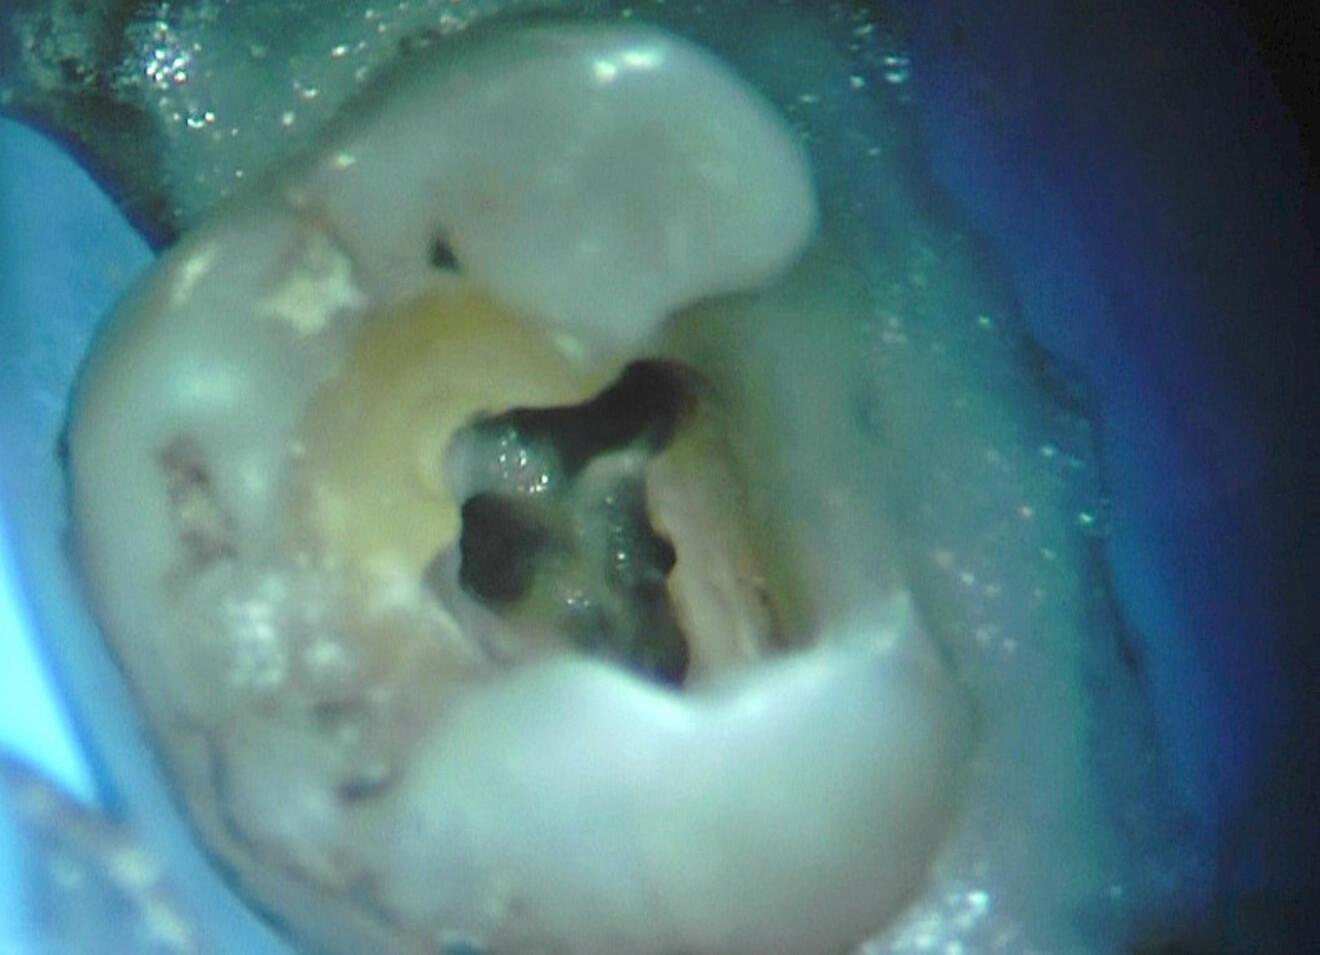

D’un point de vue pratique, la première étape consiste à réduire les dimensions du tenon s’il occupe une grande partie de la structure coronaire, de préférence en lui donnant une forme cylindrique similaire à celle d’un tenon préfabriqué. De même, une reconstitution corono-radiculaire coulée ancrée dans plusieurs canaux doit d’abord être sectionnée jusqu’au niveau du plancher de la cavité pulpaire, afin de la traiter comme un ensemble de tenons unitaires, ce qui diminue le degré de rétention global du système. La réduction du tenon doit être effectuée avec des fraises en carbure spécialement conçues pour découper le métal, sous une irrigation abondante. Les évaluations cliniques et radiographies préliminaires sont essentielles pour planifier l’angle de coupe. La procédure doit être fréquemment vérifiée et, si nécessaire, il convient d’effectuer des contrôles radiographiques avant qu’une quantité excessive de dentine ne soit sacrifiée (Figs. 1–3).